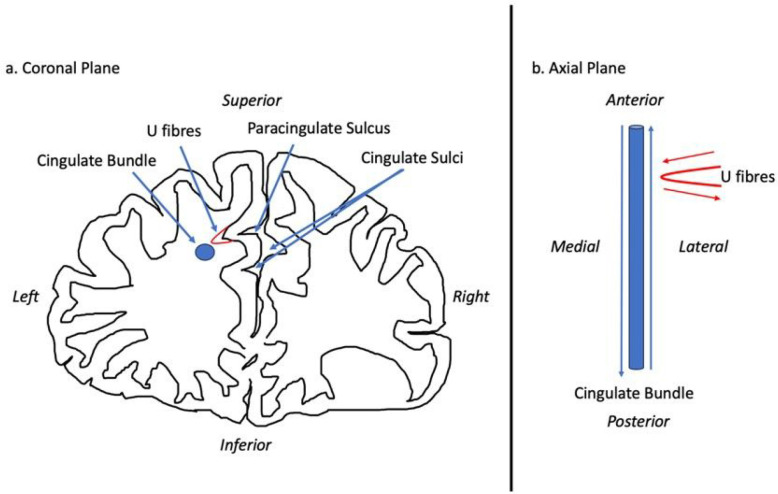

There are several ways in which PCS presence may mediate function and thus its role in disease. Cortical folding, according to the tension-based morphogenesis theory is considered to be pathway specific, partially dependent on underlying tensions between short association fibres connecting neighbouring cortical regions which shorten to reduce wiring (ref. Van Essen 1997, ref. Van Essen 2020). Reflecting this process, the PCG primarily contributes U-fibres connecting it with the AC proper which forms a localised white matter network not present where a PCS is absent (ref. Wysiadecki, Mazurek et al. 2021). There fibres may influence the observed underlying cytoarchitectural differences of the AC observed in the presence of a PCS (ref. Vogt, Nimchinsky et al. 1995).

Deep of the superficial U-fibres lie longitudinal fibres which course within the PCG when present and are identified medial and slightly inferior to the cingulate sulcus, within the cingulate gyrus where the PCS is absent (ref. Komaitis, Skandalakis et al. 2019). This tract is regarded by some as subcomponent Ia of the superior longitudinal fasciculus (SLF), (ref. Komaitis, Skandalakis et al. 2019) (ref. Wysiadecki, Mazurek et al. 2021) and by others as a division of the cingulate bundle (ref. Wu, Sun et al. 2016) or even U-fibres (ref. Maldonado, Mandonnet et al. 2012). To the best of our knowledge no neuroanatomical tracing or tractography studies have been performed with respect to PSC presence. From the perspective of intrinsically connected networks, the SLF-I is considered a major subcortical connection of the default mode network (DMN), a resting state network activated when the brain is resting (but alert) and attention is focused on internal tasks such as memory retrieval and self-reflection (ref. Yagmurlu, Middlebrooks et al. 2016). Moreover, the AC contains the cingulum bundle and represents a key hub of the Salience network (SN) (ref. Seeley, Menon et al. 2007). Operationally, the SN processes relevant stimuli by integrating sensory, emotional, and cognitive information, becoming active during tasks requiring attentional selection, task switching, and self-regulation of behavior (ref. Farb, Grady et al. 2013) (ref. Fedeli, Del Maschio et al. 2020) (ref. Seeley, Menon et al. 2007).

With respect to the tension-based morphogenesis hypothesis of gyrification, (ref. Van Essen 1997, ref. Van Essen 2020) structurally we hypothesise that presence of a PCS shall alter the SLF-I and/or cingulum bundle tracts both at a macroscopic (i.e., volume of the tracts) and microscopic (i.e., using diffusion tensor imaging metrices as proxies) level reflecting different local structural connectivity in individuals possessing a PCS. Functionally, we hypothesise that presence of a PCS shall be associated with a highly localised network component and that increased network connectivity strength shall be observed in predefined local networks (the SN and DMN).

Tract Segmentation

In the context of gyrification theories (ref. Van Essen 1997, ref. Van Essen 2020) we suggest that U-fibres, (short association fibres connecting adjacent gyri displaying a complex orientation relative to major long-white mater tracts) present in greater densities in individuals with a left PCS relative to those without may have influenced tract segment metrics. This suggestion is grounded by three principles: (1.) Inclusion of U-fibres in large tracts, referred to as a transverse inaccuracy contributes to increase the tract volume within a larger white matter tract and effect diffusivity (ref. Jbabdi and Johansen-Berg 2011). (2.) U-fibres have lower orientational coherence resulting in lower FA values. Where U-fibres are incorporated into a major tract the overall orientational coherence therefore becomes lessened resulting in a lower FA. (3.) U-fibres follow the pattern of cortical folding and as such are orientated perpendicularly to the axonal fibres of the cingulum.(ref. Movahedian Attar, Kirilina et al. 2020) U-fibre orientation and microstructure may therefore contribute to the observed increased RD in the CBP as water molecules diffuse more freely in a radial direction with respect to the CBP proper.

It is important to state that U-fibres are challenging to image and categorise due to their short length, size, and complex trajectories and though these metrics suggest their presence, a comprehensive assessment is indicated requiring ultra-high-resolution acquisitions as well as advanced imaging tractography methods specifically designed to identify and map U-fibres, which were not available in the present study.